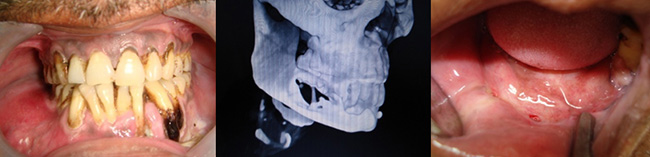

A FEW SPECIAL CASES OPERATED:

Trauma

Infections

Recent Cases Operated at Sagar Hospitals, Banashankari (December 2017 till date)